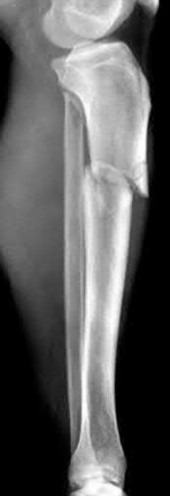

A 15-year-old boy presents with a permeative lytic lesion in the femoral diaphysis with aggressive periosteal reaction ('onion skinning'). Biopsy reveals uniform small round blue cells. Cytogenetic analysis of this tumor will most likely demonstrate which of the following translocations?

The clinical and radiographic description is classic for Ewing sarcoma. The characteristic cytogenetic abnormality is a balanced translocation t(11;22)(q24;q12), which fuses the EWS gene on chromosome 22 with the FLI1 gene on chromosome 11. This is seen in approximately 85-90% of Ewing sarcomas. t(9;22) is the Philadelphia chromosome (CML), t(X;18) is seen in synovial sarcoma, t(2;13) in alveolar rhabdomyosarcoma, and t(12;16) in myxoid liposarcoma.